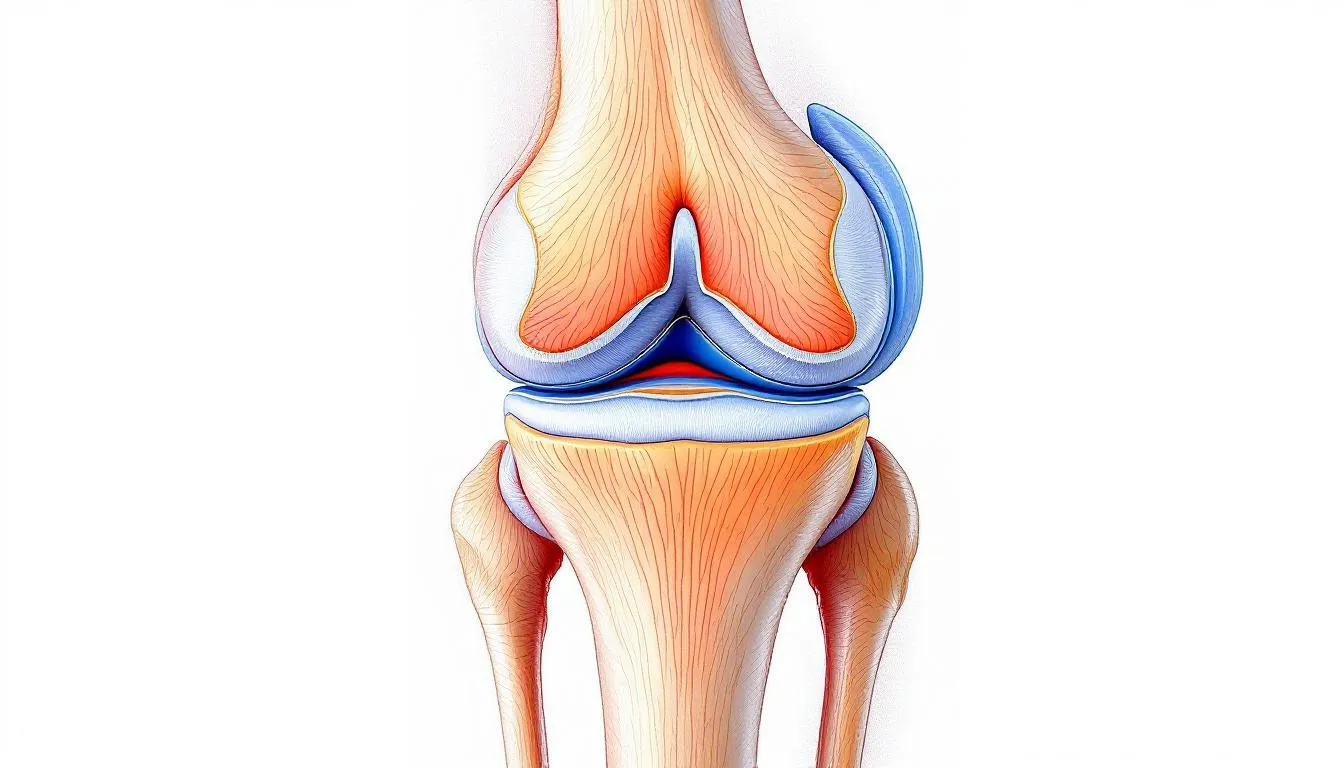

Das Kniegelenk besteht aus drei Hauptknochen: dem Oberschenkelknochen (Femur), dem Schienbein (Tibia) und der Kniescheibe (Patella). Diese Knochen bilden drei Gelenkkompartimente – das mediale (innere), laterale (äußere) und patellofemorale (zwischen Kniescheibe und Oberschenkelknochen) Kompartiment.

Der Gelenkknorpel fungiert als reibungsarme Gleitschicht zwischen den Knochenflächen und ermöglicht geschmeidige Bewegungen. Diese Knorpelschicht ist nur wenige Millimeter dick, aber entscheidend für die Funktion des Gelenks. Die Menisken wirken als Stoßdämpfer und Stabilisatoren, während die Gelenkflüssigkeit (Synovia) den Knorpel mit Nährstoffen versorgt.

Bei der Gonarthrose kommt es zum progressiven Verlust dieser Knorpelschicht, was zunächst zu Aufrauhungen, später zu tieferen Defekten bis hin zum kompletten Knorpelverlust führt. Sekundär entstehen Veränderungen am Knochen, Anbauten (Osteophyten) und Entzündungen der Gelenkschleimhaut.